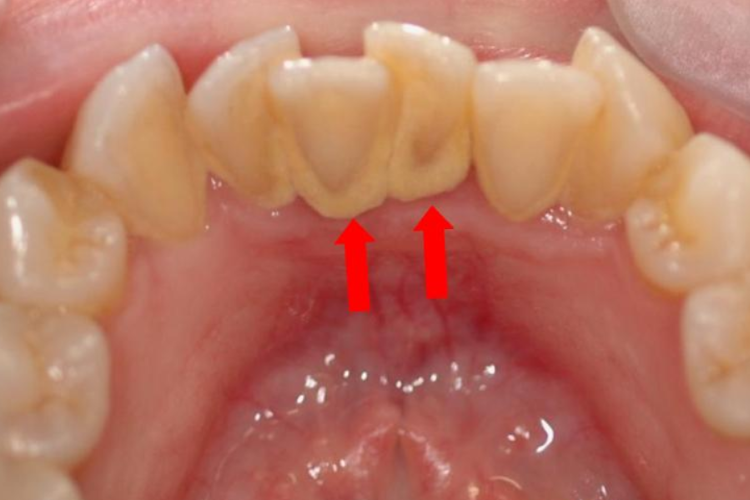

轻微牙结石表现为无软垢或少许软垢,以及少许结石,不超过牙面的1/3。软垢多附着在牙颈部,质地较软,易在刷牙、漱口时被去除。牙结石初期的颜色较浅,整体呈灰黄色、黄白色。

轻微牙结石可以就诊口腔科,由专业医生采用龈上洁治法清除牙结石,清洗完毕后还需要磨光牙面。日常应注意保持良好的口腔卫生,早晚刷牙,食后漱口,配合牙线清理食物残渣等,建议少吃精细食品。